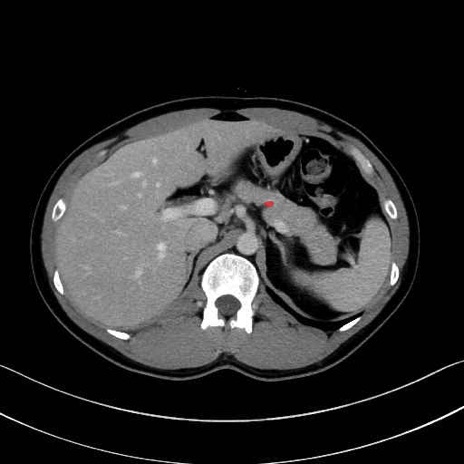

【症例】20歳代 男性 スクリーニング

■起始:典型的には腹腔動脈幹(celiac trunk)から左胃動脈・総肝動脈とともに三分岐し、脾動脈は左後上方へ向かう。

■走行:膵上縁または膵実質背側を蛇行しながら左方へ進み、膵尾部近傍で脾門へ至る。蛇行の程度は個体差が大きい。

■終枝:脾門部で複数の終末枝に分かれ、上極・下極枝や脾門枝群を形成する。胃短動脈群や左胃大網動脈はしばしば脾動脈から分岐する。